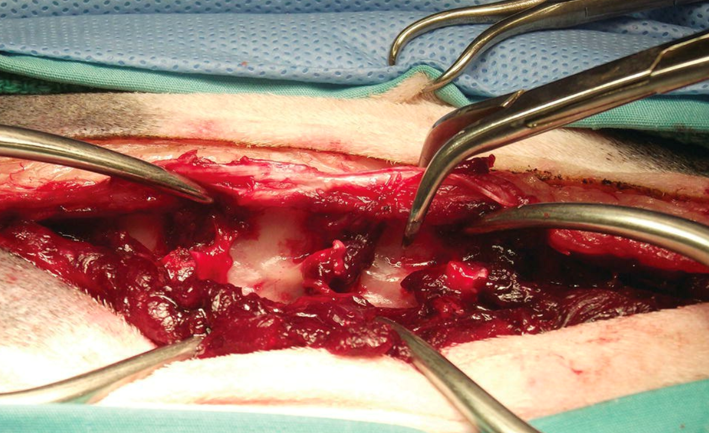

감압술은 일반적으로 피부와 근막을 길게 절개를 하고 spine 주변 muscle을 분리한 뒤 측면을 노출하고 수술이 진행되게 됩니다.

따라서 주변 근육 및 구조물을 필연적으로 손상시키게 되고 이는 술 후 통증과 근 위축 등으로 이어지게 됩니다. (사진1)

사진1. 감압술을 시행하기 위한 절개창